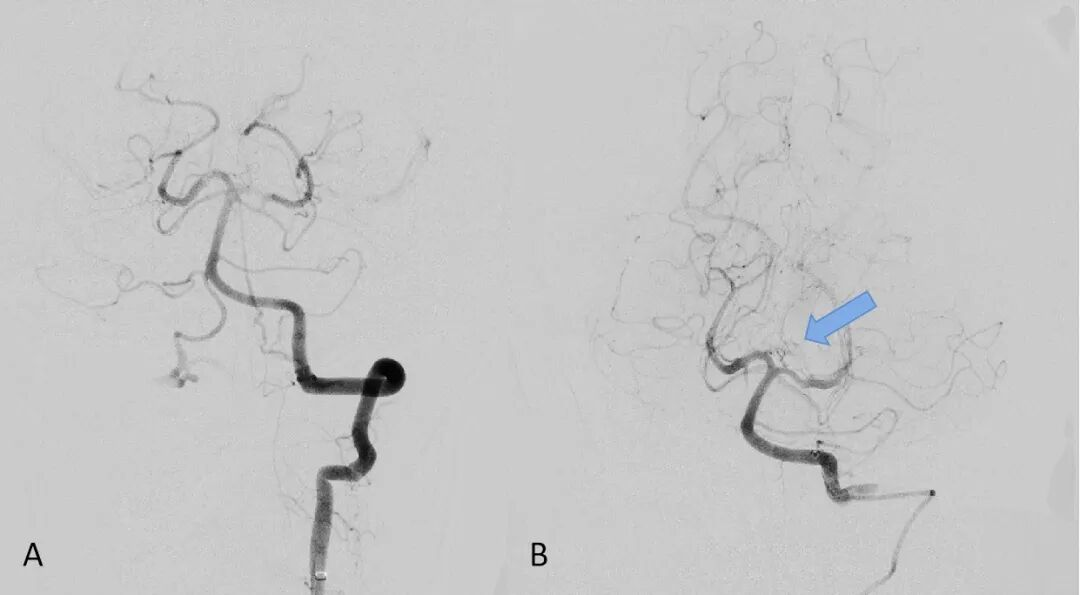

▲A显示左侧大脑后动脉P1段显影模糊、Percheron动脉显影不清;B显示Percheron动脉正常显影

在神经内科二区主任朱敏真指导下,张文胜主治医师、古鸿力主治医师紧急为患者实施了脑血管造影和血管内介入治疗术。术中发现左侧大脑后动脉P1段显影模糊,考虑局部存在血栓,同时Percheron动脉显影不清,有急诊取栓和动脉溶栓的指征,与患者家属充分沟通风险和获益后,患者家属同意急诊取栓和动脉溶栓治疗。经过血栓抽吸、动脉溶栓后,抽出少量血栓,同时可见Percheron动脉正常显影,股动脉穿刺到血管完全恢复耗时65分钟。手术成功后,复查颅脑CT未见出血。